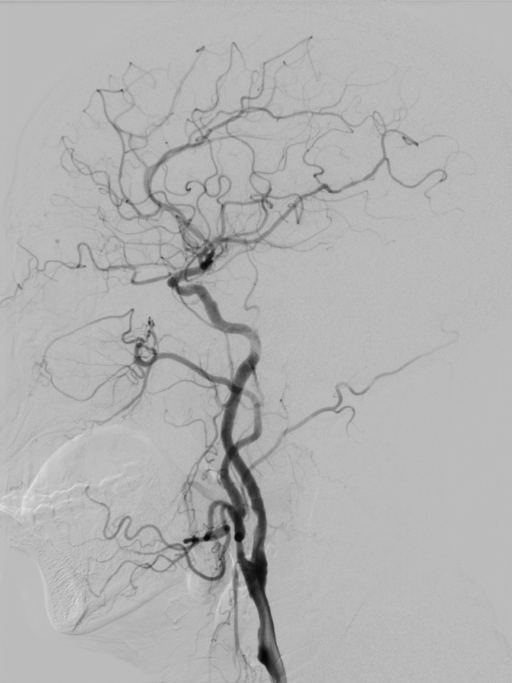

桡动脉入路行DSA:右侧颈内动脉C1段重度狭窄。

右侧桡动脉穿刺,置入7F薄壁鞘,造影示右侧颈内动脉C1段重度狭窄,狭窄率约90%,狭窄长度约22mm。通过加硬泥鳅导丝、125cm SIM2造影导管辅助,将5.5F Introsky X导管鞘置于右侧颈总动脉远端,选择KangFly微导丝携带Spider FX保护伞通过狭窄病变后释放保护伞,5.0*30mm球囊预扩张,置入9*40mm自膨式支架。

术后即刻影像:造影见右侧颈内动脉C1段血流通畅,mTICI3级。